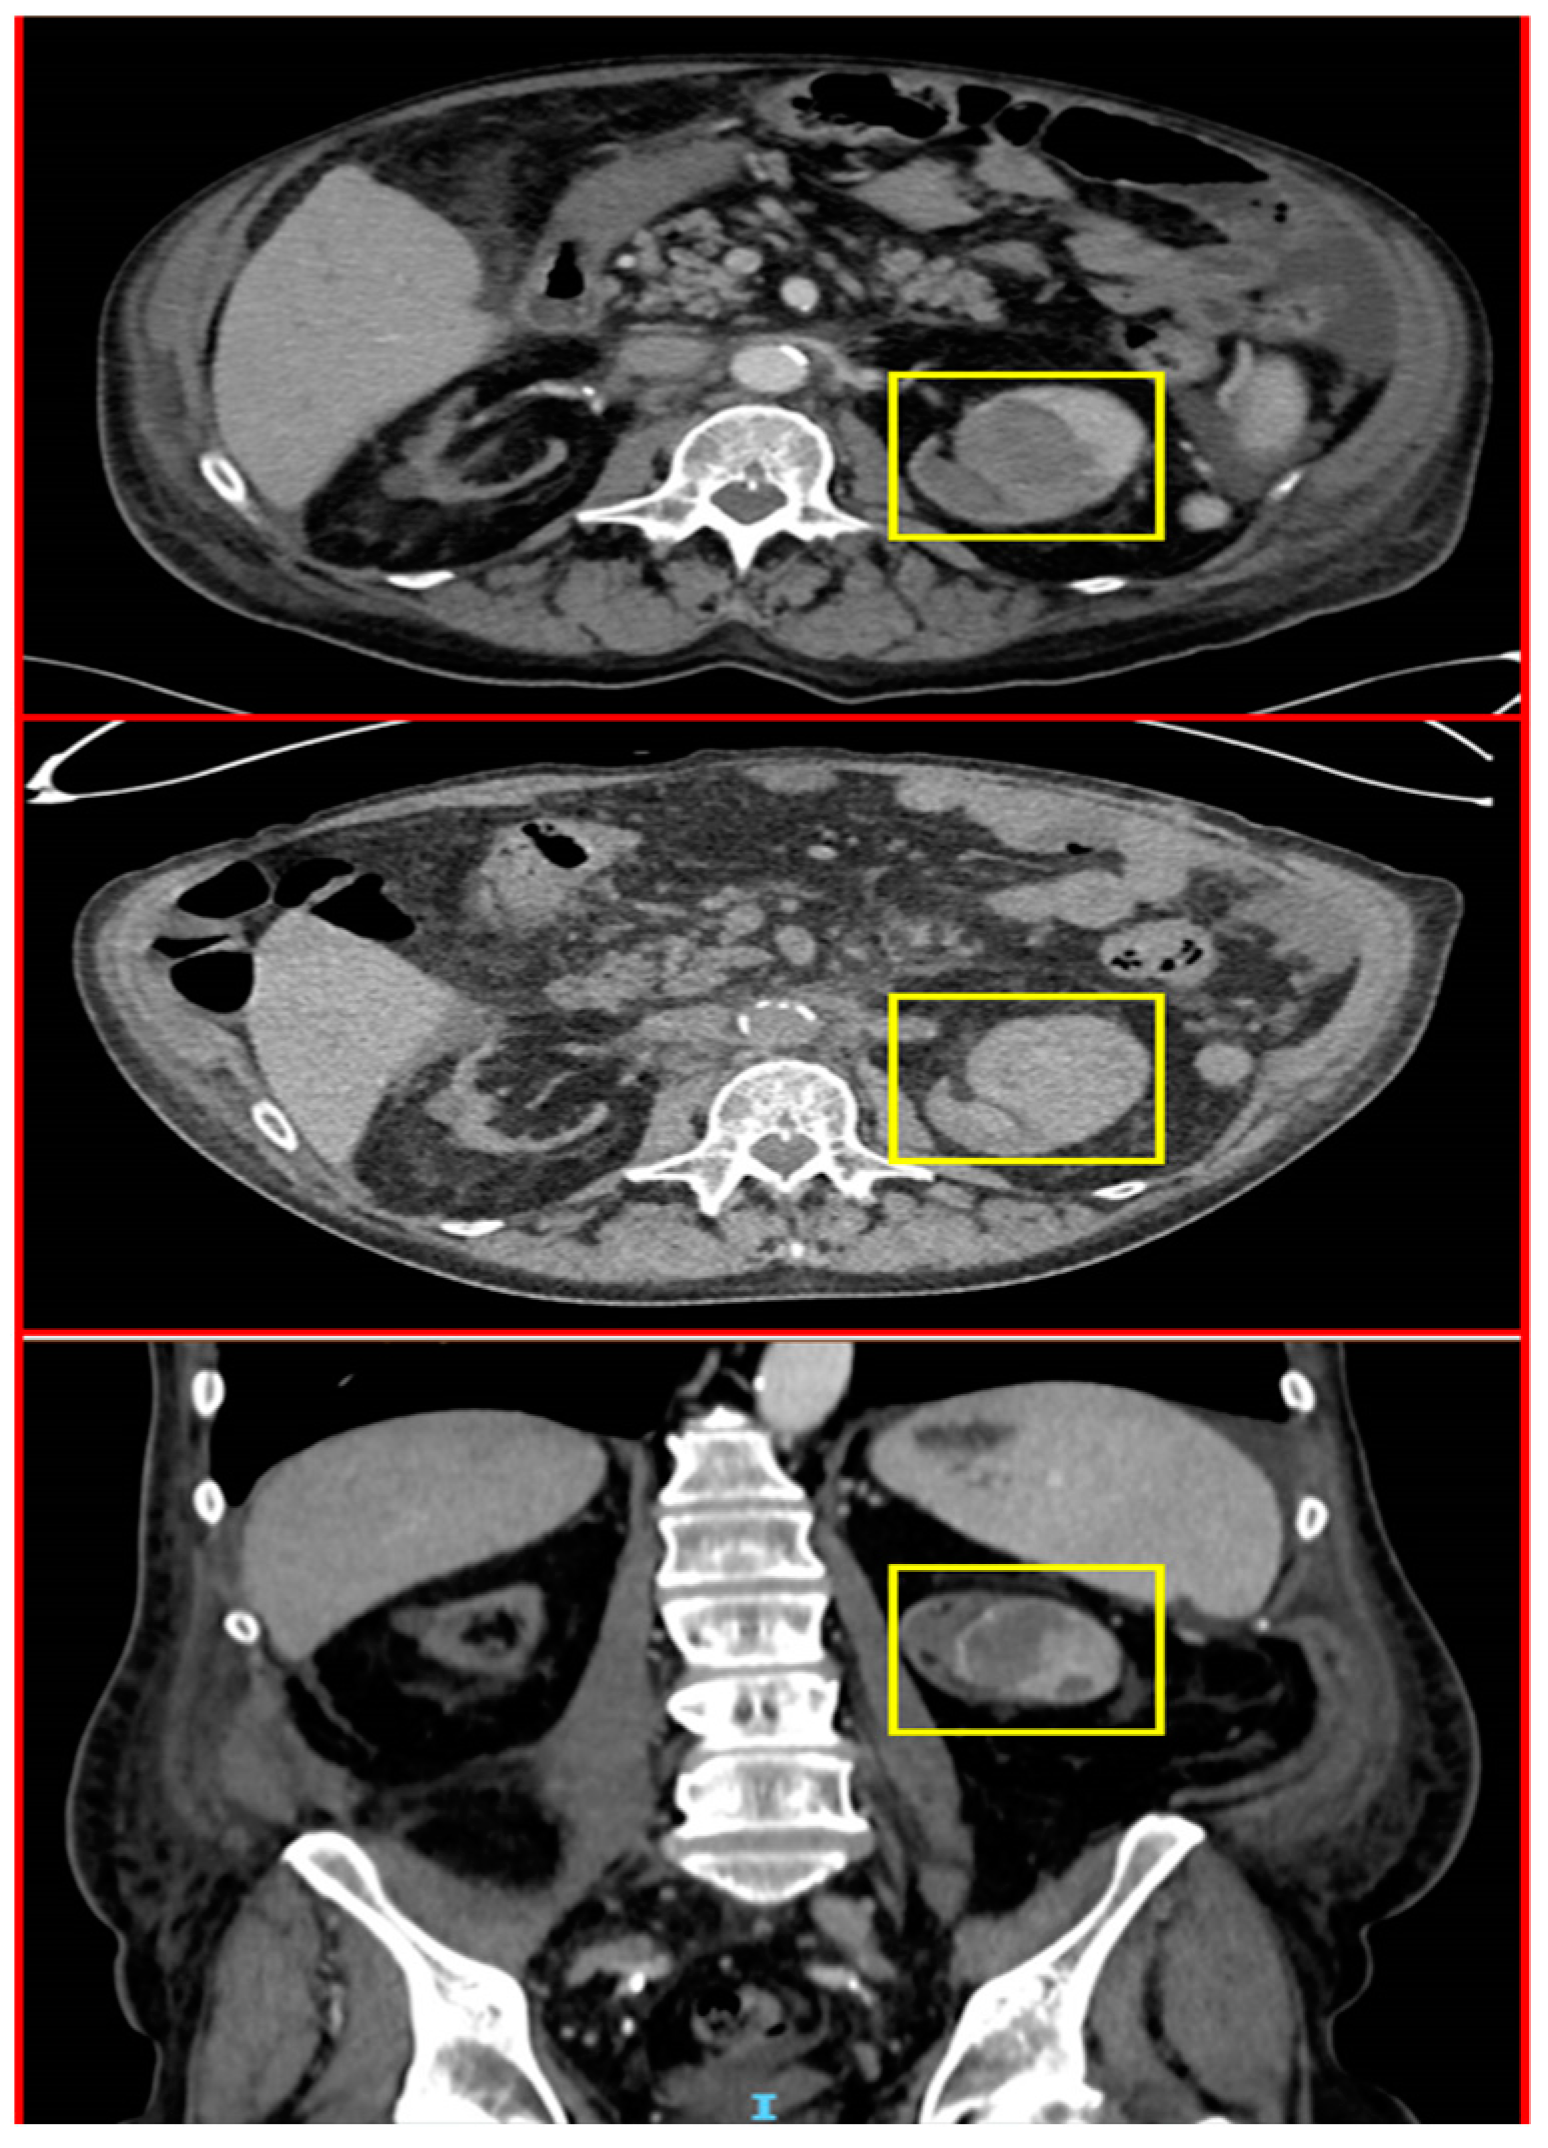

2.4. A Male with Melanoma Metastasized to the Pancreas

| 4 | 68 | M | Metastatic Melanoma | Pancreas | CT Histopathology | Ipilimumab/Nivolumab |